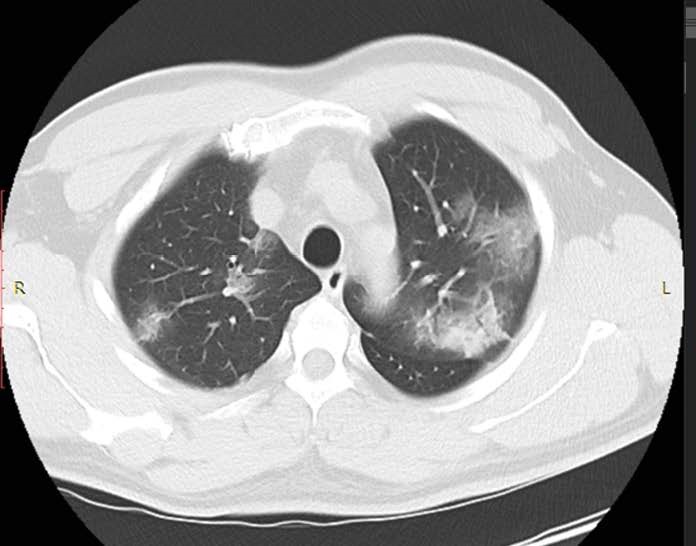

• the computed tomography system 64-slice manufactured by NIPK Electron Co. for primary assessment and differential diagnostics of chest diseases, as well as for revealing concomitant diseases. The modular CT unit can be equipped with a computed tomography system with another slice number as an option. According to the interim methodological guidelines “Prevention, Diagnostics, and Treatment of a new Coronavirus Infection” developed by the Ministry of Health of Russia, a CT scan is considered one of the basic methods of COVID-19 diagnosis.

The computed tomography system 64-slice (CT) installed in the module unit is equipped with a wide set of specialized software applications for diagnostic imaging in patients with respiratory disorders, vascular abnormalities, cancer, as well as for assessment of cerebral, renal, and hepatic blood supply. Thanks to this, CT is in high demand not only during the COVID-19 pandemic.